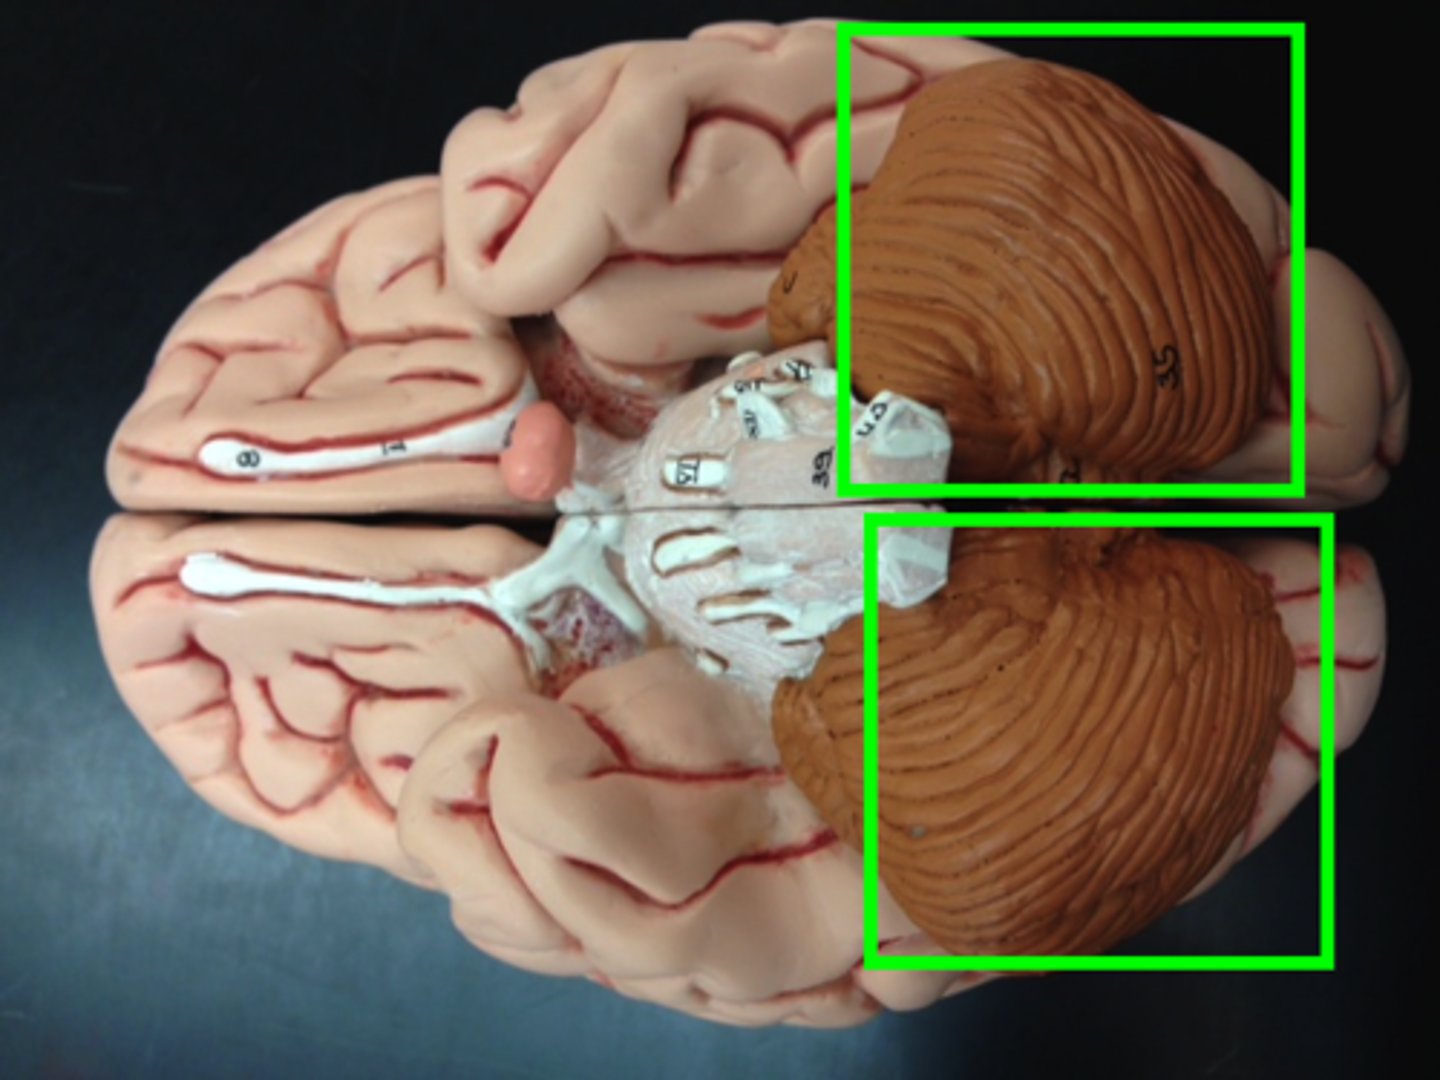

transverse fissure

separates cerebrum from cerebellum

cerebellum

cerebellar hemisphere

vermis

Connects the two hemispheres of the cerebellum